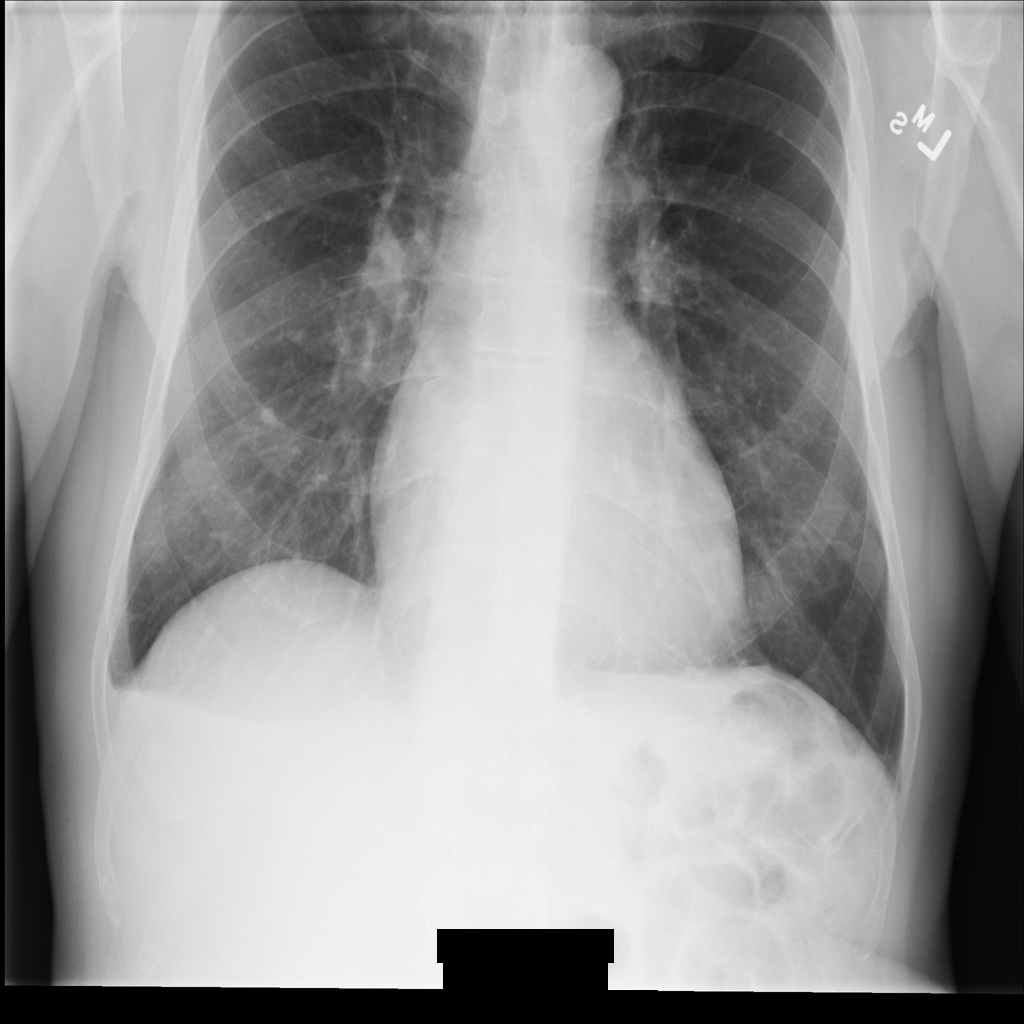

Dopo aver rimosso i dati identificativi dall'immagine utilizzando REDACT_SENSITIVE_TEXT_CLEAN_DESCRIPTORS, l'immagine

ha questo aspetto. Nota che non tutto il testo incorporato nella parte inferiore dell'immagine è stato oscurato. Il testo Female viene ancora visualizzato perché

PatientSex (0010,0040) non è uno degli infoType DICOM predefiniti.

REDACT_SENSITIVE_TEXT_CLEAN_DESCRIPTORS.Anonimizzare i tag DICOM